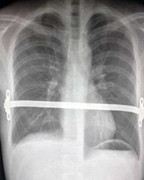

(VTC News) - Một người đàn ông có lồng ngực bóp bẹp tim và phổi đã được cứu sống sau khi các bác sĩ đưa vào các khe xương sườn một thanh kim loại.